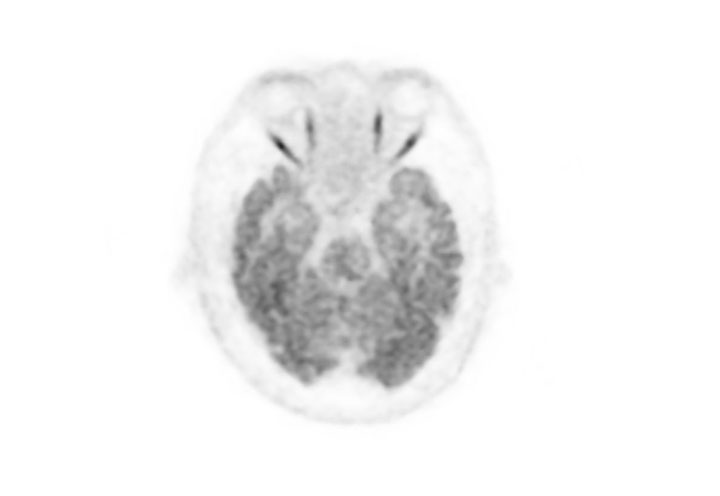

Head / Case2 : FDG

Courtesy : Kindai University Hospital

- Imaging protocol

- Injected dose: 3.29 MBq/kg, 18F-FDG

- Uptake time: 38 minutes

- Scan time: 30 minutes